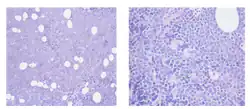

La bendamustine est un médicament de chimiothérapie utilisé dans le traitement de la leucémie myéloïde chronique, des myélomes multiples, et du lymphome non-Hodgkinien. Elle est commercialisée sous le nom Levact en France, et Treanda, Treakisym, Ribomustin dans le reste du monde.